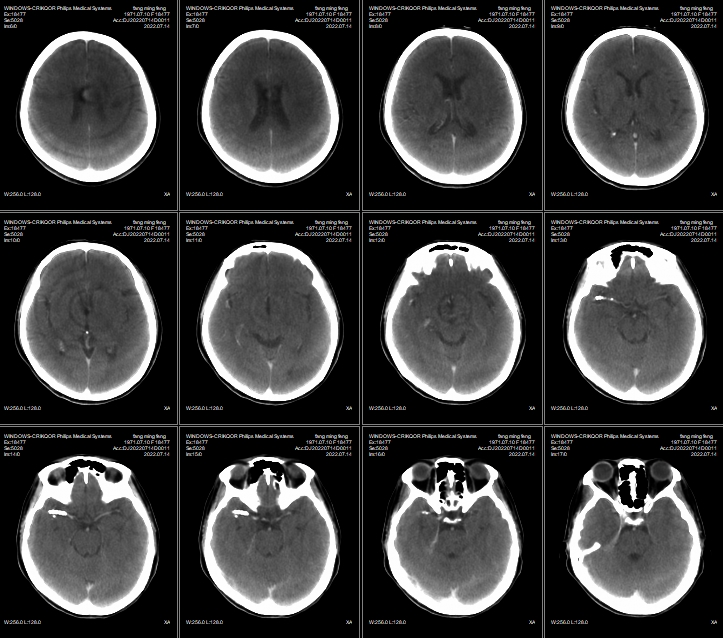

术后即刻正侧位造影显示载瘤动脉及远端分支显影无异常,瘤囊内可见明显造影剂滞留;Xper-CT未见出血。